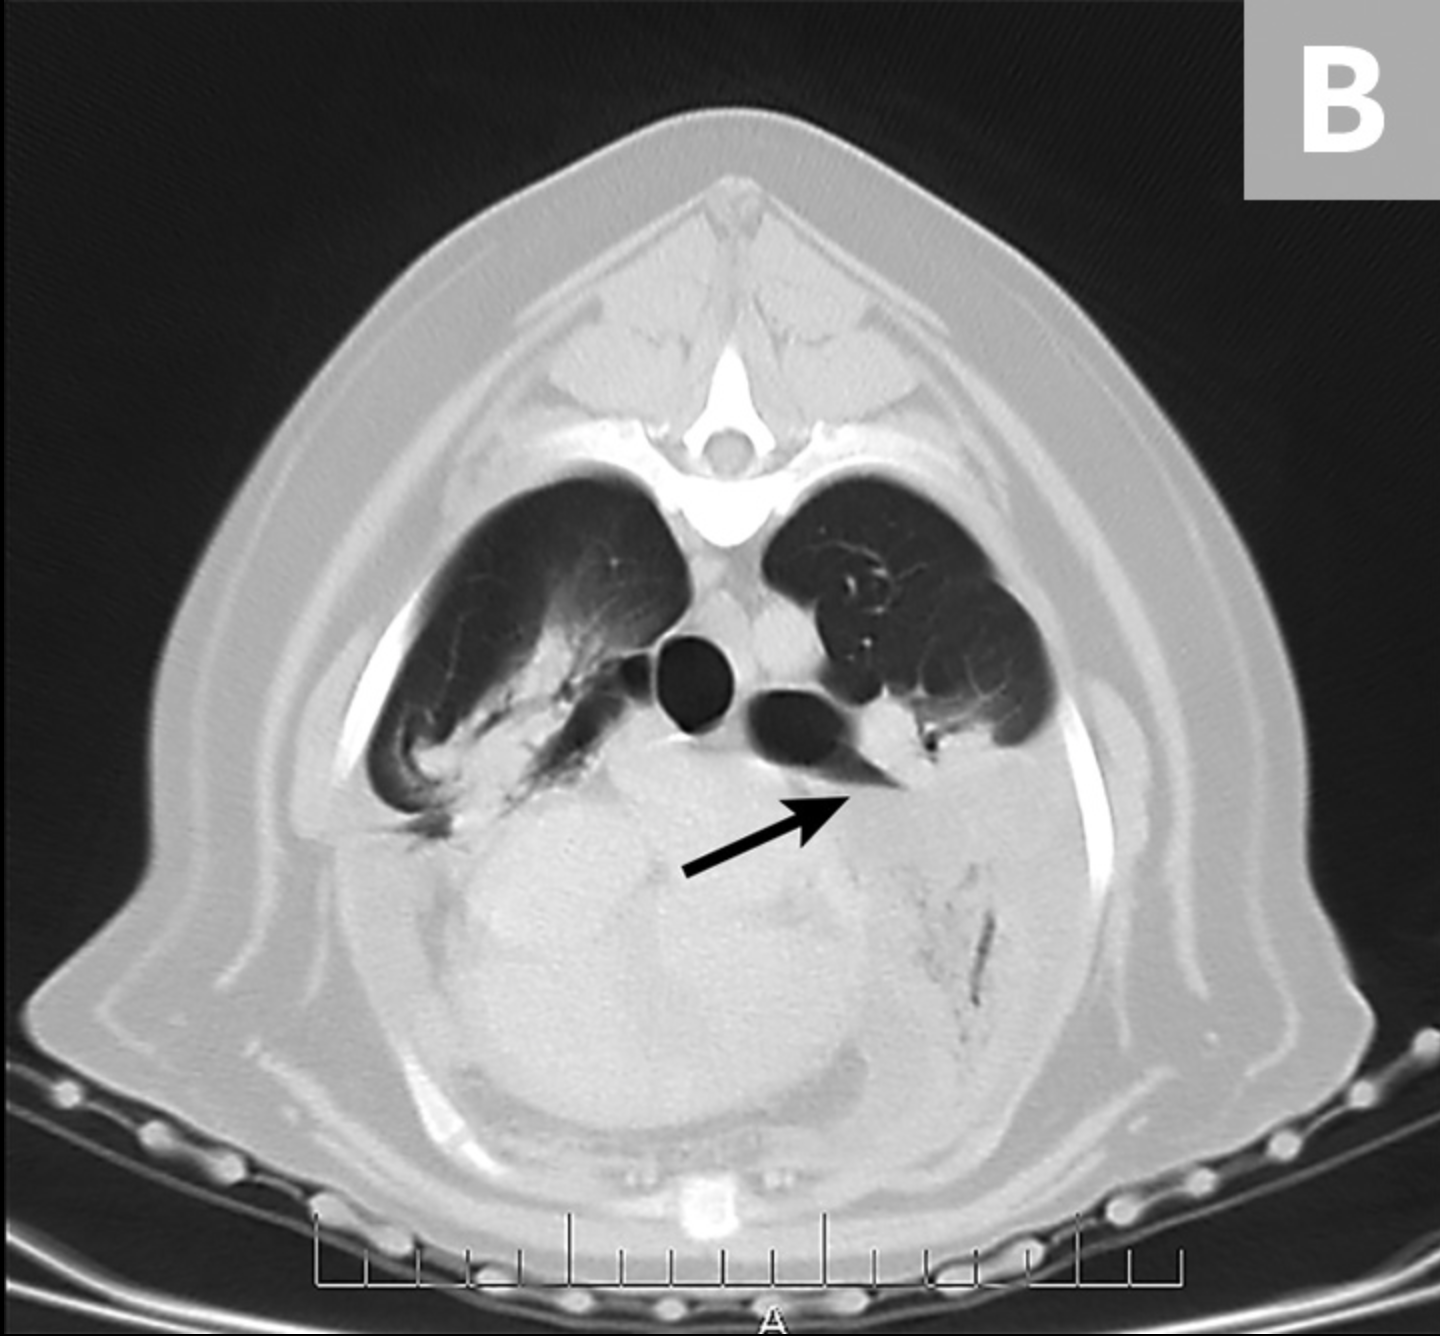

La TC mostró derrame pleural moderado bilateral con una apariencia anormal del lóbulo craneal izquierdo del pulmón, colecciones de gases punteados y truncamiento del bronquio que sugirió LLT (Figura 4).